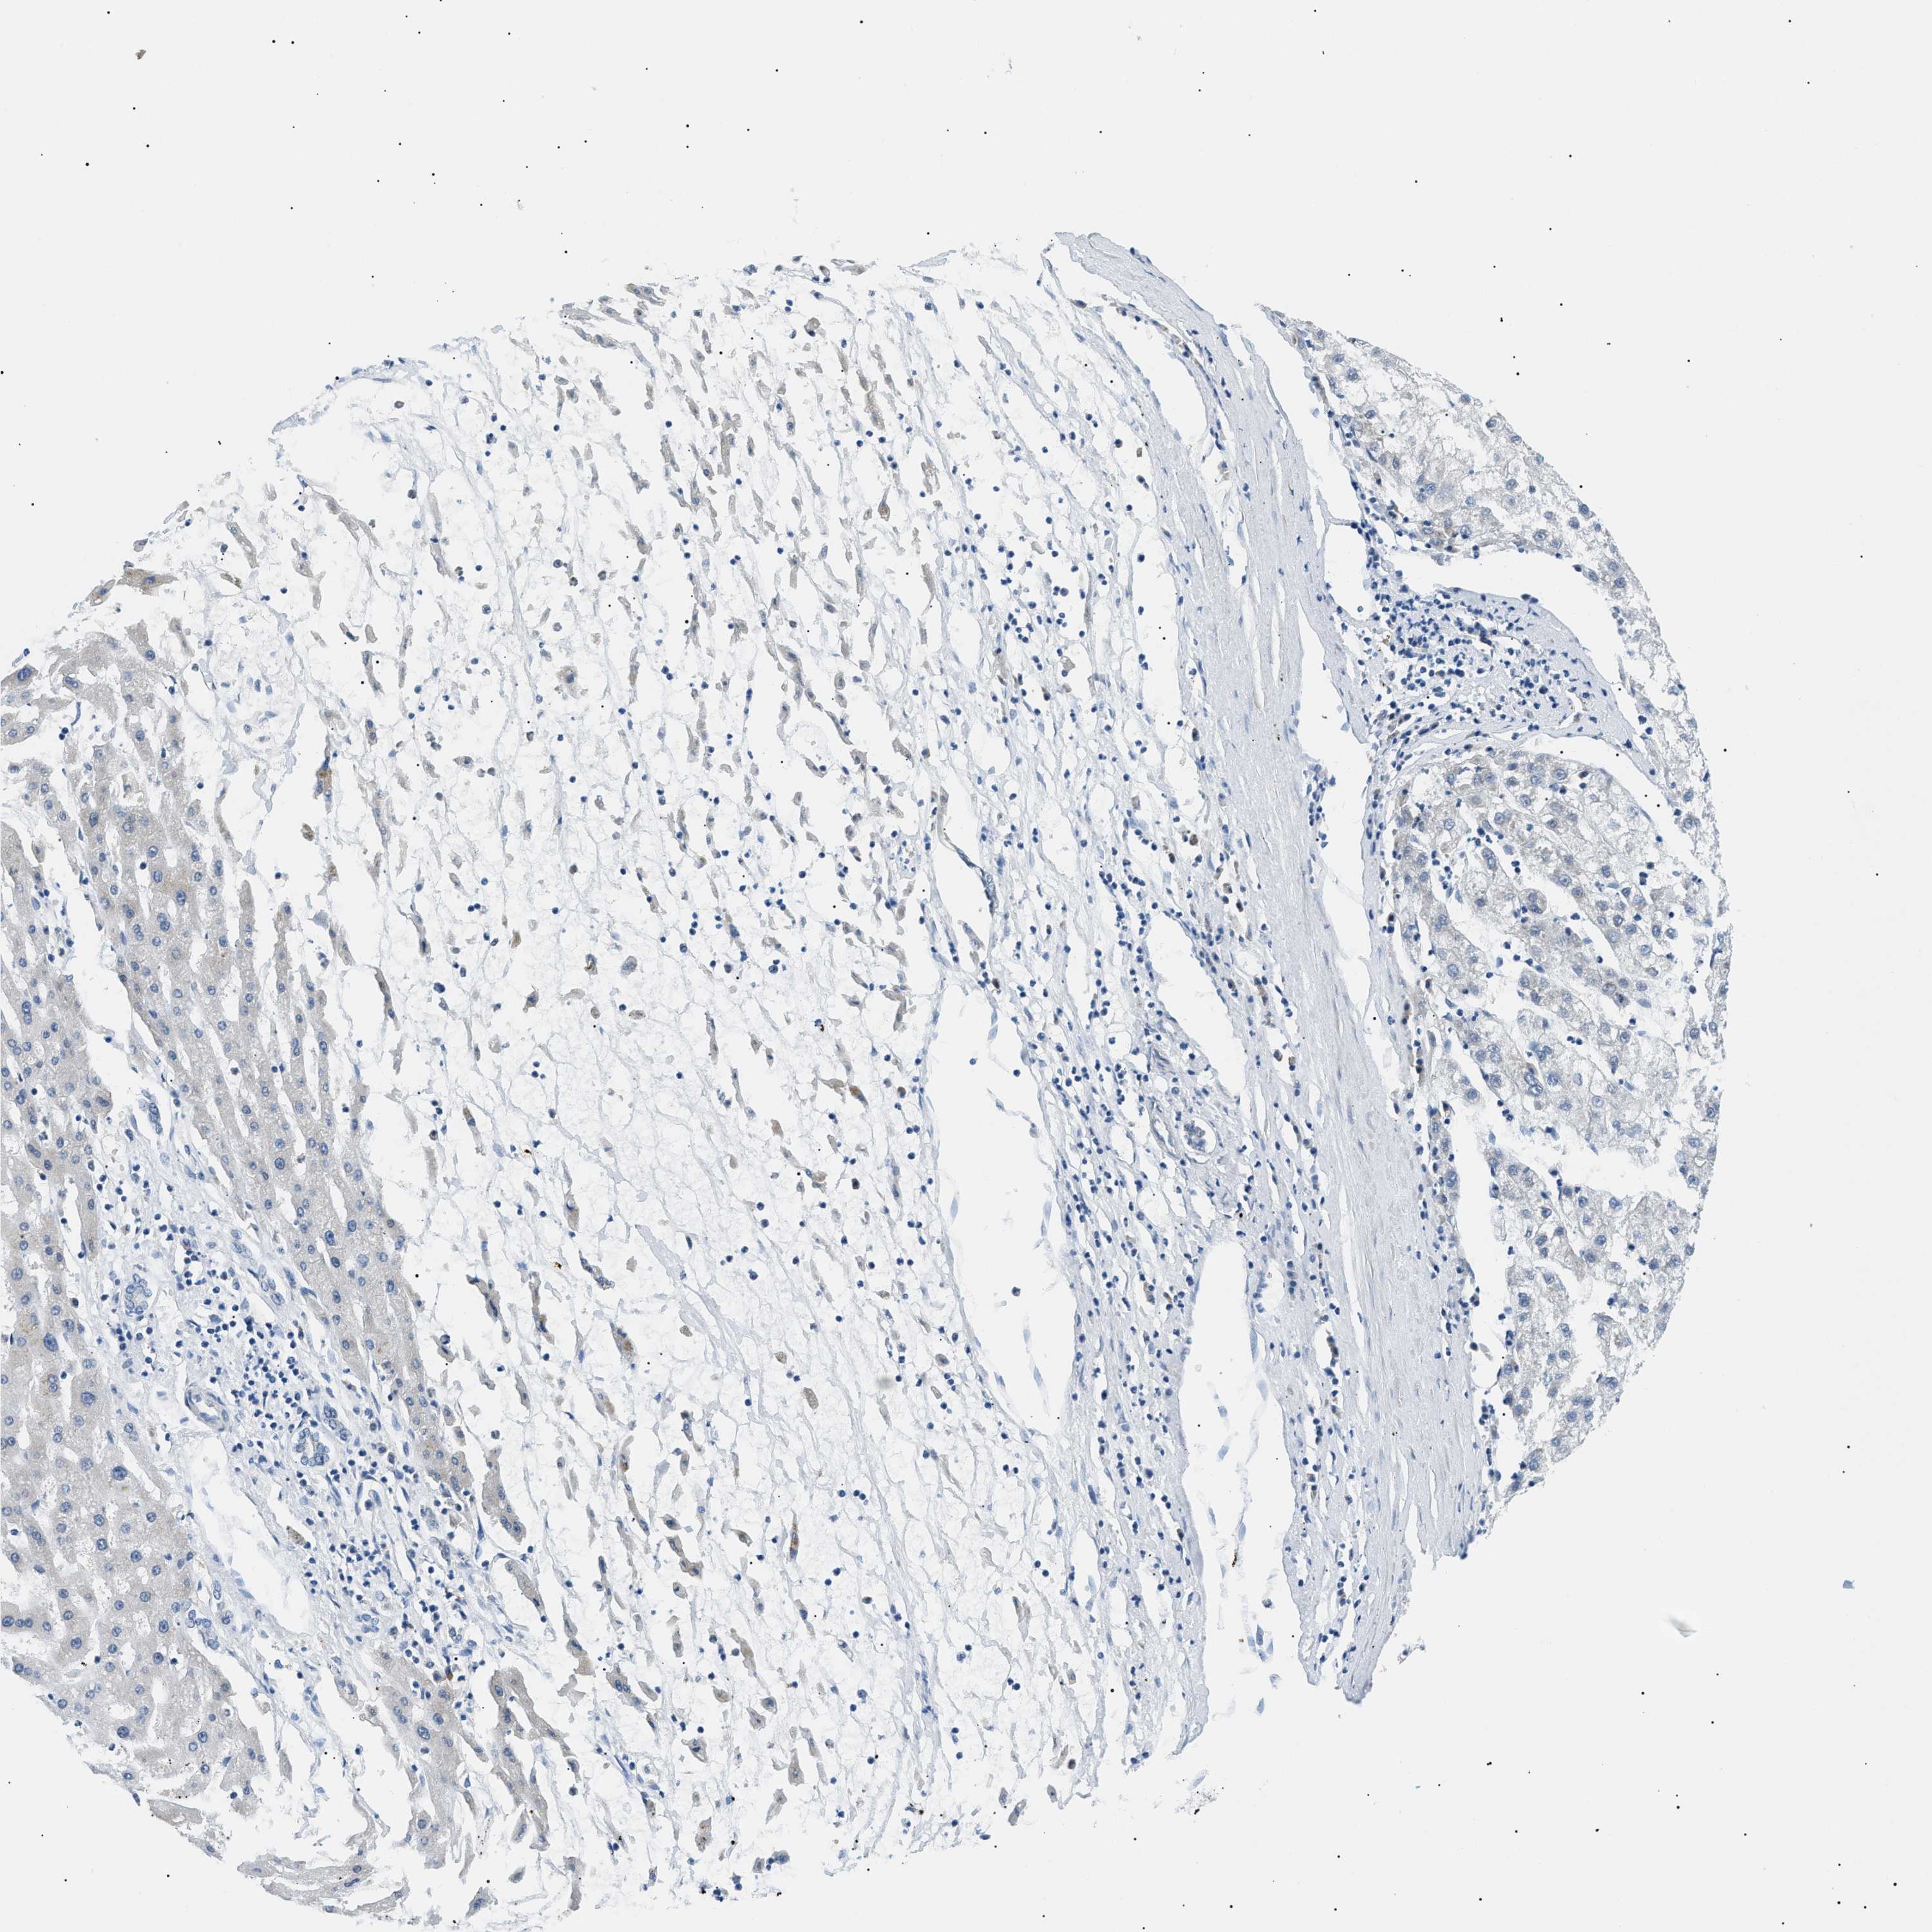

LIVER CANCER - Protein expressioni

A mouse-over function shows sample information and annotation data. Click on an image to view it in a full screen mode. Samples can be filtered based on level of antibody staining by selecting one or several of the following categories: high, medium, low and not detected. The assay and annotation is described here.

Note that samples used for immunohistochemistry by the Human Protein Atlas do not correspond to samples in the TCGA dataset.

Antibody stainingi

Antibody staining in the annotated cell types in the current human tissue is reported as not detected, low, medium, or high, based on conventional immunohistochemistry profiling in selected tissues. This score is based on the combination of the staining intensity and fraction of stained cells.

Each image is clickable and will lead to virtual microscopy that enables deeper exploration of all samples and also displays staining intensity scores, fraction scores and subcellular localization as well as patient and tissue information for each sample.

Antibody HPA062997

Antibody CAB014874

Staining

High

Medium

Low

Not detected

Intensity

Strong

Moderate

Weak

Negative

Quantity

>75%

75%-25%

<25%

None

Location

Nuclear

Cytoplasmic/membranous

Cytoplasmic/membranous,nuclear

Carcinoma, Hepatocellular, NOS

Cholangiocarcinoma